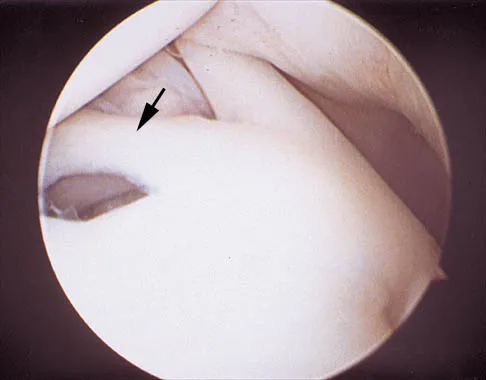

Question 91High Yield

A 24-year-old athlete has a painful right shoulder. Figure 30 shows an intra-articular photograph that was obtained through a posterior portal during arthroscopy; the labrum is indicated by the arrow. Based on these findings, management should consist of

Explanation